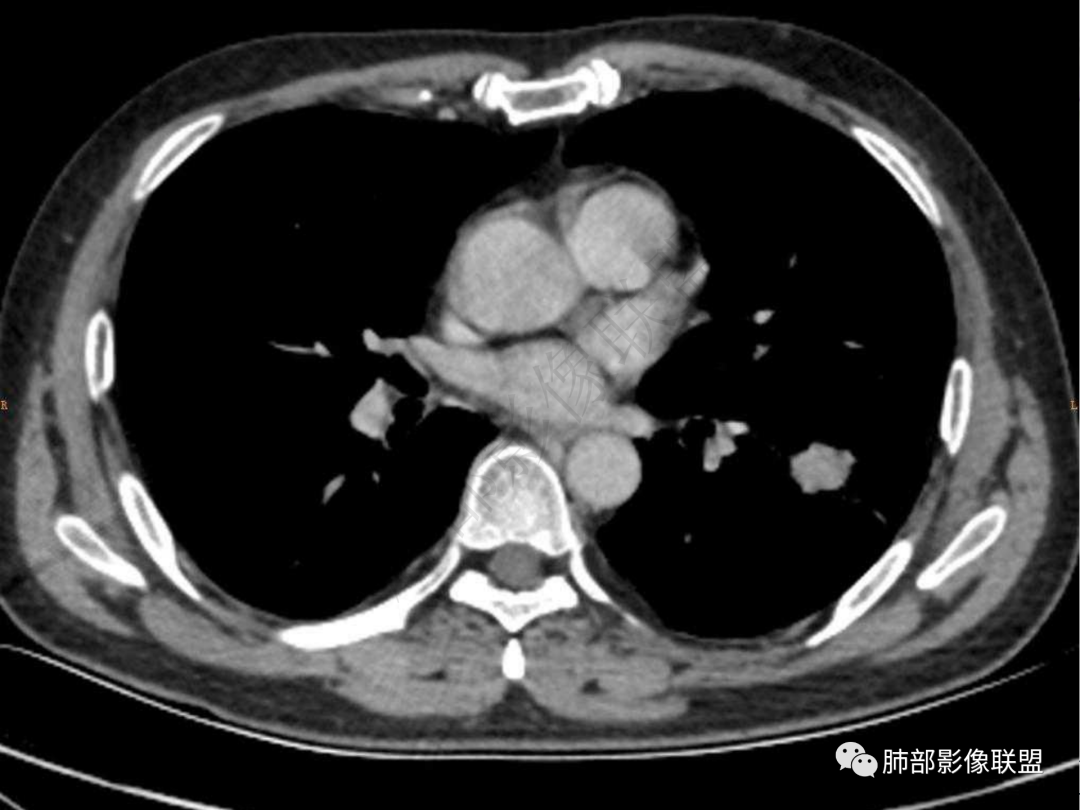

2.左肺下叶团片影,跨背段及内前基底段,实性部分类椭圆形,密度不甚均匀,可见毛刺及棘状突起,未见典型分叶及胸膜凹陷。病灶上下缘可见相应肺段支气管旁进侧出,管壁轻度增厚,未见狭窄阻塞。

4.实性部分不均匀环形强化并显示一小范围低密度坏死区或空洞。较之肺窗,整体纵隔窗范围较小,提示病灶并不十分密实。抑或为不同时段图像。

5.双肺门及纵隔未见增大淋巴结。未见胸腔积液。